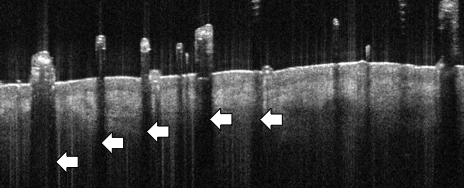

- Hair seen protruding from epidermal surface

- Surface hairs can be easily identified by their hyperreflective structure above the skin surface

- Hairs are comprised of keratin and cast a shadow on underlying features